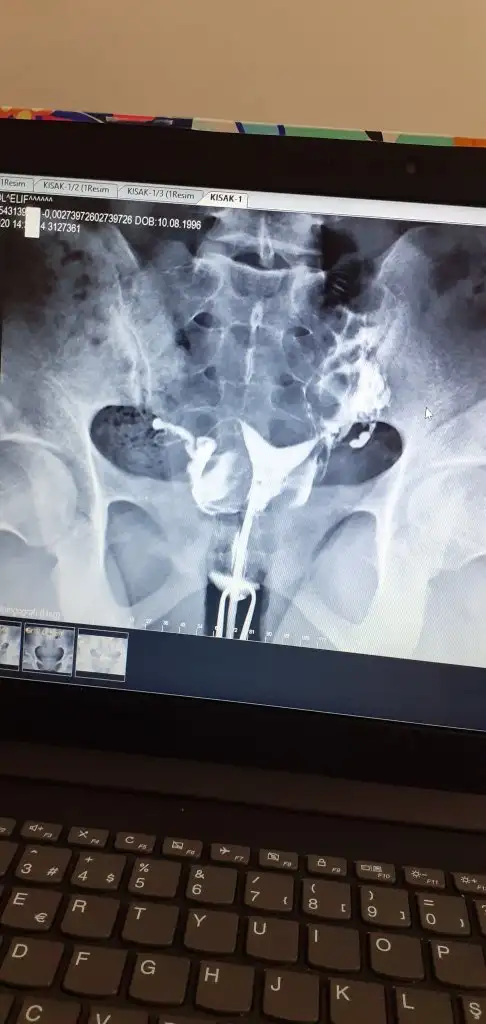

Aynı benimde böyle çıktı dün hsgde size ne dedi doktor

Büyük problem yaratmaz dediAynı benimde böyle çıktı dün hsgde size ne dedi doktor

Şuan tüp bebek tedavisindeyim benim filmim bu şekilde histeroskobi dedi Dr kararsizimBüyük problem yaratmaz dedi